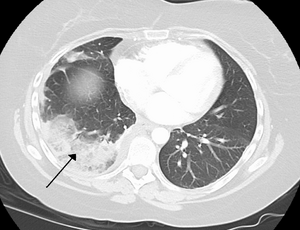

تصوير مقطعي محوسب للصدر (نافذة الرئة المحورية).

تصوير مقطعي محوسب للصدر (نافذة الرئة التاجية).